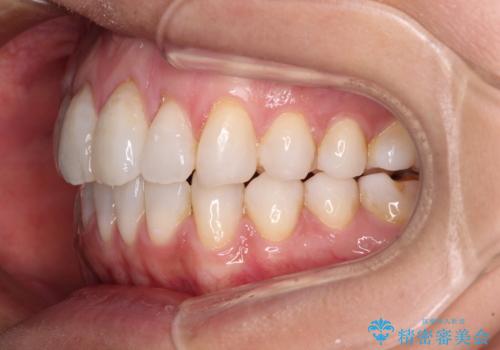

少しだけ飛び出た前歯を整えたい インビザラインによる矯正治療

- 少しだけ前に飛び出ている前歯を気にして来院された患者様です。

上顎歯列全体を後方に移動させる必要があり、インビザライン単体での治療は困難と判断し、補助装置により左右側方歯列を移動させた後にインビザラインを用いることとしました。

インビザライン単独でも上顎歯列全体を後方移動することで臼歯の咬み合わせを改善できる場合もあります。しかしながら、矯正治療は当初設定したゴールに到達する必要があり、今回のような場合ではインビザライン単独では達成の可能性が低くなるので、補助装置を使用して、より確実に治療を行うこととしています。